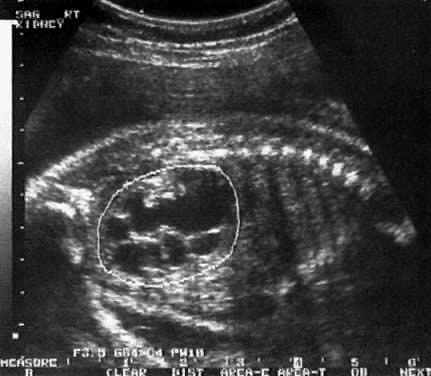

2- Prenatal ultrasonografi (gebelik sırasında yapılan ultrasonografi) genişlemiş böbrekleri olan bir fetusu (bebeği) gösterebilir. Bu durumda bebeğin doğumundan birkaç hafta sonra voiding sistoüretrografı yapılır. Çoğunda idrar yolu enfeksiyonu tekrar gelişebileceğinden, bebekler ve küçük çocuklardaki reflünün tanı ve tedavisi özellikle önemlidir. Değerlendirme yapana dek bir çocuğun iki ya da daha fazla sayıda idrar yolu enfeksiyonu geçirmesini beklemek, kalıcı böbrek hasarı ve nedbeleşmesi riskini artırır.

Vezikoüreteral reflü değerlendirmesinde ultrasonografi (USG) diğer önemli tanı aracıdır. Voiding sistoüretrografı öncesinde rutin yapılması önerilir. Radyasyon içermeyen ve ağrısız bir çalışmadır. Böbrek, üreterler ve mesaneyi göstererek idrar yolu enfeksiyonuna neden olabilecek bazı anormalliklerin ve böbrekteki genişlemenin (hidronefroz) tanınmasını sağlar. Yukarıda sayılan testler anormalse ya da tekrarlayan ateşli enfeksiyonlar olmuşsa böbrek sintigrafisi (damar yolundan radyoaktif madde verilerek böbrek görüntülenmesi) yapılabilir. Sintigrafik inceleme, böbreklerin gerçek fonksiyon ve boşalmasını daha iyi gösterir. Önceki idrar yolu enfeksiyonları sonucu böbreklerde kalıcı hasar ve/veya skarlaşma oluşup oluşmadığını ortaya koyar. Ayrıca voiding sistoüretrografiye benzer şekilde yapılan, reflünün tanısı ve kardeşlerde reflü taranması amacıyla kullanılan nükleer sistogram testi de nükleer tıp uzmanlarınca yapılmaktadır. Reflü bir ölçek üzerinde 1 (en hafif) ile 5 (en ciddi) arasında derecelendirilir. Bu derecelendirme tedavi kararı almada ve seyri tahmin etmede yardımcıdır. Daha ciddi derecedeki reflüler tedavi edilmezlerse daha yüksek böbrek hasar riski taşırlar ve kendiliğinden iyileşme oranlan daha düşüktür.